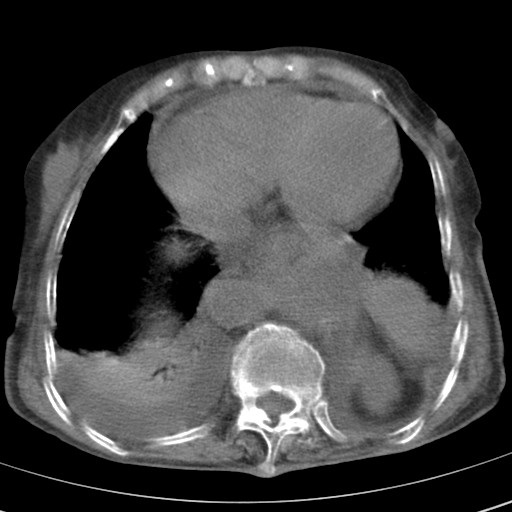

标题: CT21467:女,93岁,摔伤后检查。

女,93岁,摔伤后检查。

右肺炎症,心功能不全伴双侧胸腔积液,右下肺膨胀不全,食管裂孔疝,冠脉钙化,心包少量积液,左侧肋骨骨折,请上传骨窗.

食管裂孔疝

创伤性湿肺,双侧胸腔积液。可能有食管裂孔疝,进一步检查。骨折有无根据自己的机器及片子再仔细看吧。

右侧锁骨\\肩胛骨骨折、右侧湿肺,心功能不全伴双侧胸腔积液,右下肺膨胀不全,左膈破裂或食管裂孔疝,冠脉钙化,心包少量积液,请上传骨窗.

右肺炎症,心功能不全伴双侧胸腔积液,右下肺膨胀不全,食管裂孔疝,冠脉钙化,心包少量积液,左侧肋骨骨折,右肩甲骨粉碎性骨折。93岁,高寿哇!

右肺炎症,心功能不全伴双侧胸腔积液,右下肺膨胀不全,食管裂孔疝,冠脉钙化,心包少量积液,左侧肋骨骨折,右肩甲骨粉碎性骨折。